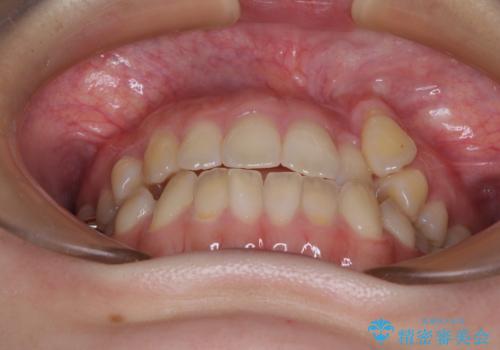

急速拡大装置 狭い上顎骨を拡大してワイヤー装置で八重歯を短期間治療

- 上顎の八重歯やデコボコを気にして来院された患者様です。

上顎歯列が狭窄していたため、急速拡大装置により上顎骨を側方に拡大しながら、ワイヤー装置にて矯正治療を行うこととしました。

上顎骨を拡大することで、八重歯やデコボコを歯列に収めることができ、下顎の歯が外に位置していた奥歯の咬み合わせも改善することができました。

スペースも短期間に獲得できるため、1年程度で治療を終えることができました。